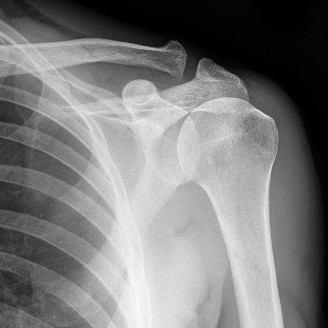

CASE 11 A 33-year-old male presents to the ED after a fall during a soccer game. He reports significant right shoulder pain and limited ROM. An x-ray taken in the ED is shown below (Fig. 2–29).

Figure 2–29

The correct answer is (A). The ED image shown in Figure 2–29 includes only an AP view of the right shoulder. In the setting of an acute injury and pain, technicians may be hesitant to obtain additional views. A single view, however, is insufficient to diagnose either a fracture, as orthogonal views are required, or a shoulder dislocation which is best seen on an axillary view (see Fig. 2–30). Answers B and C are inappropriate as a diagnosis has not been established yet and a dislocation or fracture must be conclusively ruled out. Answers D and E may be options that are exercised in the clinic but do not represent the next step in the management of this patient.

--- _Figure 2–30_A: Axillary view. B: Axillary view with annotations. Traumatic anterior instability is a common shoulder problem with an estimated incidence of 1.7%. This term encompasses both frank dislocations that require a manual reduction as well as incomplete subluxations that spontaneously reduce. It is particularly common in the young and athletic population, and it is significantly more common than other forms of instability including posterior or multidirectional instability. Understanding the natural history of anterior instability is important, as it serves as a guide to treatment. Young patients have a very high risk of recurrence; patients <20 years old have a 90% recurrence risk, between 20 and 40 years old have a 60% recurrence risk, and >40 years old have a 10% risk. Recurrent events are a predictor for arthritis and necessitate aggressive treatment, particularly in the young patient.